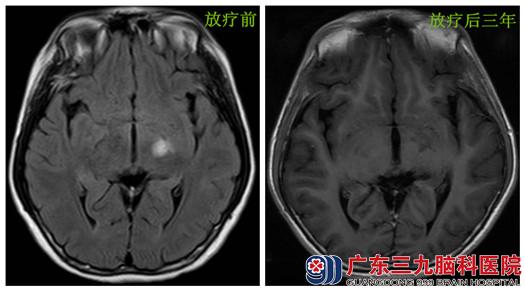

【生殖细胞瘤放疗后3年未复发】

患者吴某,男,10岁,2011年7月起出现多饮多尿,每日饮水约4L,未予重视。2012年2月无明显诱因出现右侧肢体活动欠灵活,握笔及走路不稳,伴口角向左歪斜,症状逐渐加重。于当地医院行头颅MR示左侧基底节区异常信号影,当地以脱髓鞘病变对症治疗,治疗后肢体激励稍好转。3月肢体患者乏力反复出现,不能握拳,随即来我院就诊。经腰穿查脑脊液绒毛膜粗性腺激素(HCG)稍高,于3月19日开始行诊断性放疗,放疗10次后,复查脑脊液HCG水平较前下降,患者症状较前好转,生殖细胞瘤诊断成立。随后行全中枢放疗,放疗结束复查头颅MR定位片提示与放疗前MR对比,现左侧基底节区水肿范围明显缩小,异常强化基本消失,脑脊液HCG水平恢复正常,患者右侧肢体活动较前灵活,口角歪斜程度较前好转。

现患者放疗后3年返院复查:神志清楚,言语流利,右侧肢体肌力V-级,左侧肢体肌力正常,期间未再出现肢体乏力反复,头颅及脊髓MR未见明显肿瘤复发征象,患者正常上学。